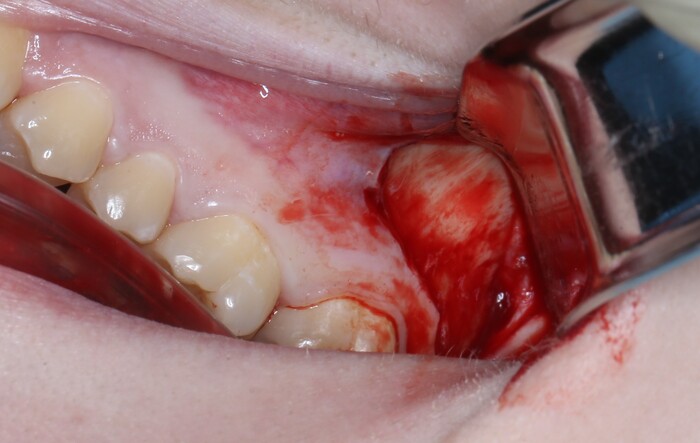

Вот так выглядит область, в которую мы планируем вмешаться:

Я сделал анестезию, разрез и отслоил слизисто-надкостнечный лоскут: